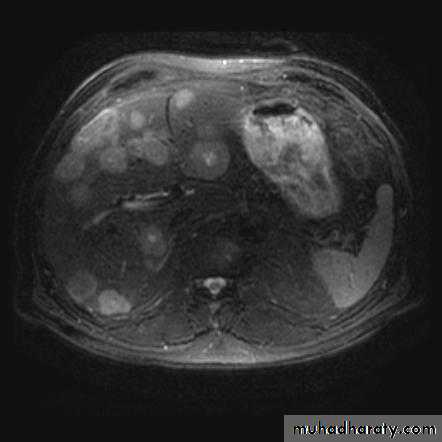

Hydatid cysts may be single or multiple; a few show calcified walls. Daughter cysts may be seen within a main cyst at both US and CT.